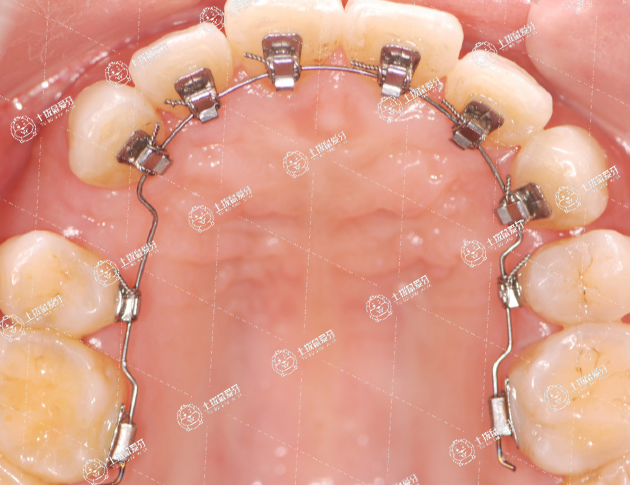

如果牙齒畸形比較嚴(yán)重的情況下,佩戴的時(shí)間一般會(huì)比較長。牙齒深覆合可能是遺傳因素所引起,可能是長時(shí)間不良咀嚼習(xí)慣所造成,會(huì)造成口腔內(nèi)咬合不良,還會(huì)影響到正常咀嚼功能,在早期發(fā)現(xiàn)疾病時(shí),可以通過佩戴牙套進(jìn)行矯正,牙套分為隱形牙套和金屬牙套。佩戴牙套矯正過程中需要養(yǎng)成按時(shí)刷牙習(xí)慣,避免食物殘?jiān)罱?/p>

牙性前牙深覆頜主要是因?yàn)樯舷骂M前牙位置或牙的數(shù)目異常造成,如上頜前牙唇向、下頜前牙舌向錯(cuò)位等。需要進(jìn)行正畸矯正治療,一般為幾萬元。一般隱形矯正治療費(fèi)用比托槽矯正治療高。